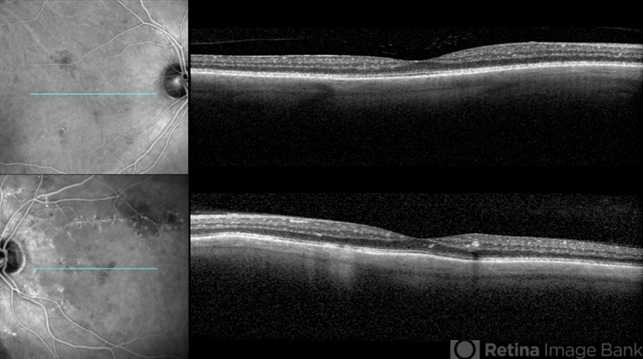

- A 59-year-old female with Lipemia Retinalis